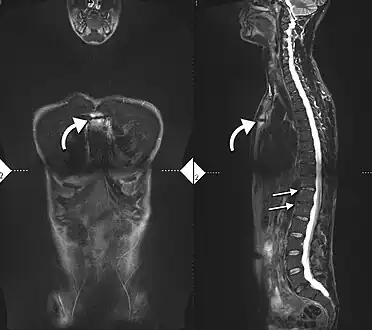

Imaging

X-rays

The earliest changes demonstrable by plain x–ray shows erosions and sclerosis in sacroiliac joints. Progression of the erosions leads to widening of the joint space and bony sclerosis. X-ray spine can reveal squaring of vertebrae with bony spur formation called syndesmophyte. This causes the bamboo spine appearance. A drawback of X-ray diagnosis is the signs and symptoms of AS have usually been established as long as 7–10 years prior to X-ray-evident changes occurring on a plain film X-ray, which means a delay of as long as 10 years before adequate therapies can be introduced.[21]

Options for earlier diagnosis are tomography and MRI of the sacroiliac joints, but the reliability of these tests is still unclear.

-

Lateral X-ray of the mid back in ankylosing spondylitis -

Lateral X-ray of the neck in ankylosing spondylitisImaging -

X-ray showing bamboo spine in a person with ankylosing spondylitis -

CT scan showing bamboo spine in ankylosing spondylitis -

T1-weighted MRI with fat suppression after administration of gadolinium contrast showing sacroiliitis in a person with ankylosing spondylitis -

34-year-old male with AS. Inflammatory lesions of the anterior chest wall are shown. Inflammatory changes are seen in the lower thoracic spine and L1